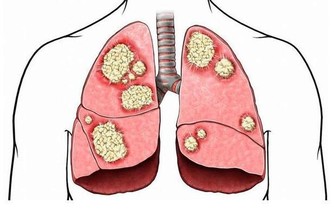

膝關節是全身關節中滑膜最多的關節,故滑膜炎以膝關節較為多見。膝關節滑膜炎通常指膝部的滑膜受到刺激而引發炎症,進而分泌液失調在關節腔內形成積液的一種病變,包括非特異性滑膜炎和特異性滑膜炎。當關節受外在性和內在性因素影響時,滑膜發生反應,引起充血或水腫,並且滲出液體,表現為關節腫脹、疼痛、關節腔積液、活動受限等。如不及時治療,會影響關節正常活動,並造成關節的破壞甚至病廢。

4.膝關節炎

膝關節炎是一種由膝關節軟骨退行性改變引起的疾病,引起疾病的原因包括年齡、性別、遺傳因素、重複性關節應激和代謝紊亂,病變影響軟骨、軟骨下骨和關節組織,主要特徵為關節軟骨的漸進性破壞與軟骨下骨的硬化,骨贅形成,與滑膜炎有關,臨床症狀表現為劇烈疼痛、關節僵硬、關節活動度顯著降低,有甚者可能進一步導致殘疾發生,嚴重影響患者的生活質量。